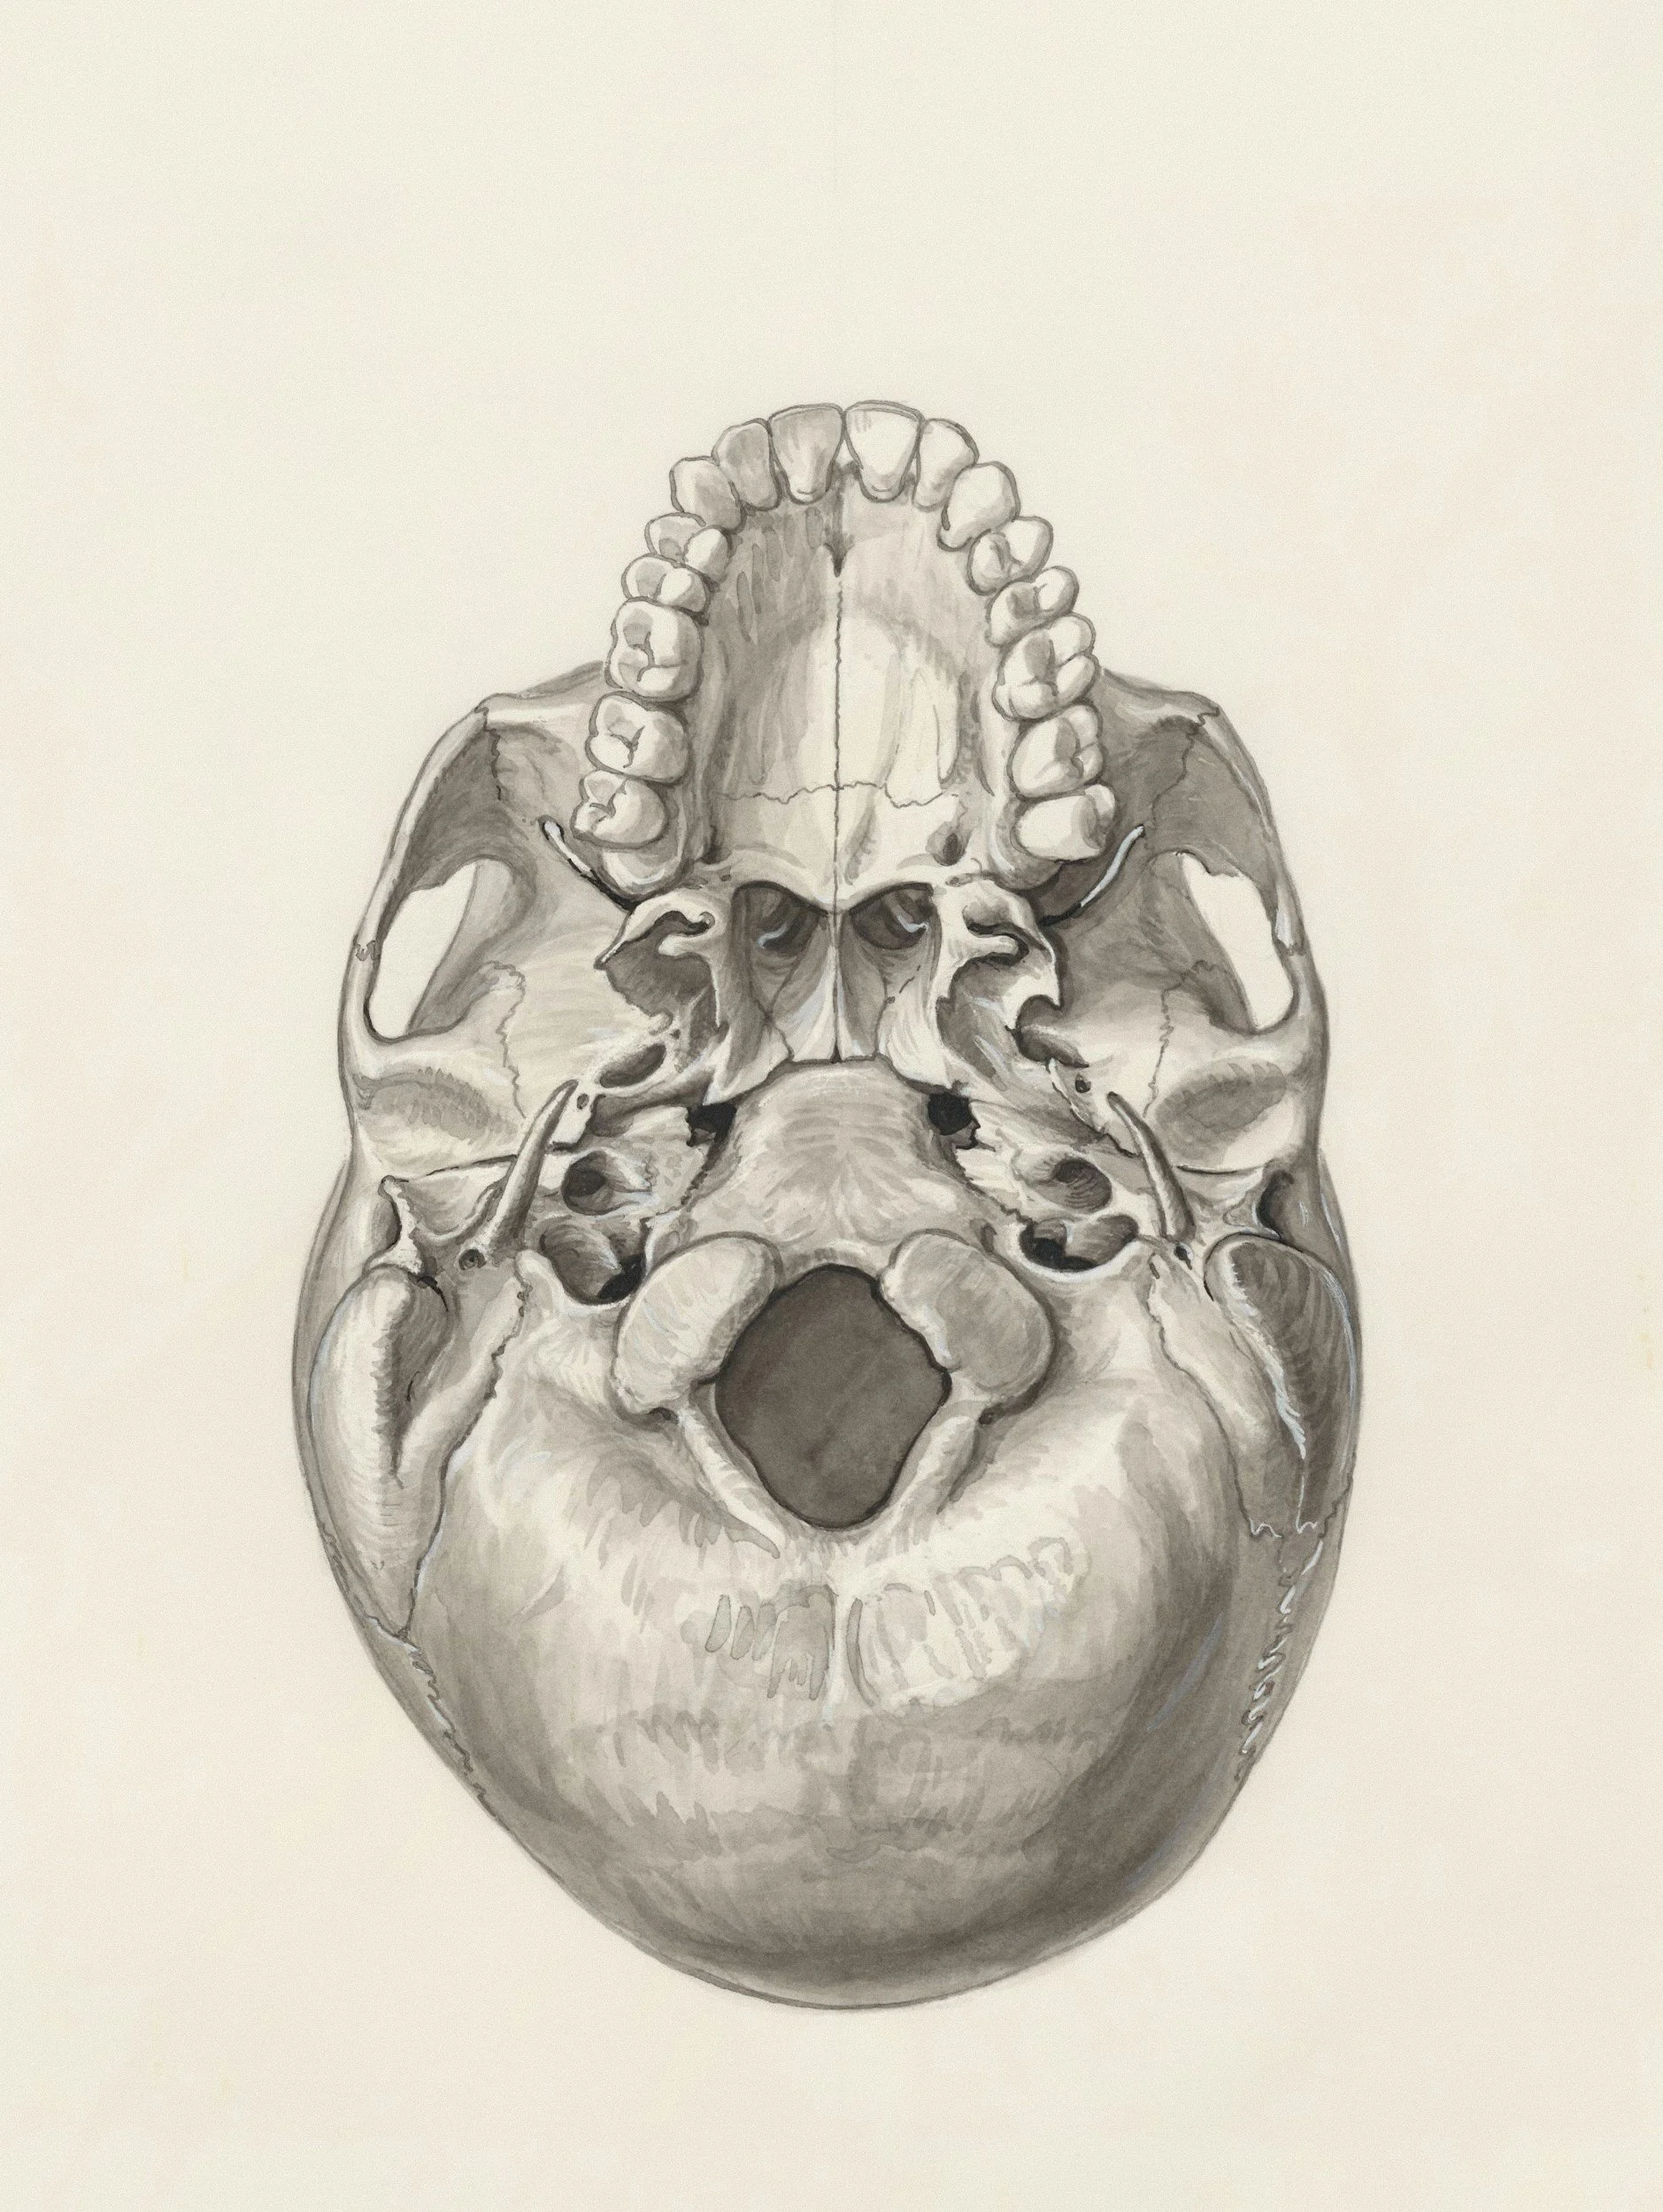

Chordomas & Chrondrosarcomas

Matei Banu

Matei Banu is an Assistant Professor, neurosurgeon and researcher at Stanford University. He completed his neurosurgery residency at Columbia University, New York Presbyterian hospital following medical training in Romania. He the pursued specialised skull base and neuro-oncology training with dedicated fellowships at MD Anderson Cancer centre in Houston, Texas and Stanford University. He is activity involved in research on techniques for resection and treatment of skull base pathology. Here he discusses his approach to chordomas and chondrosarcomas.